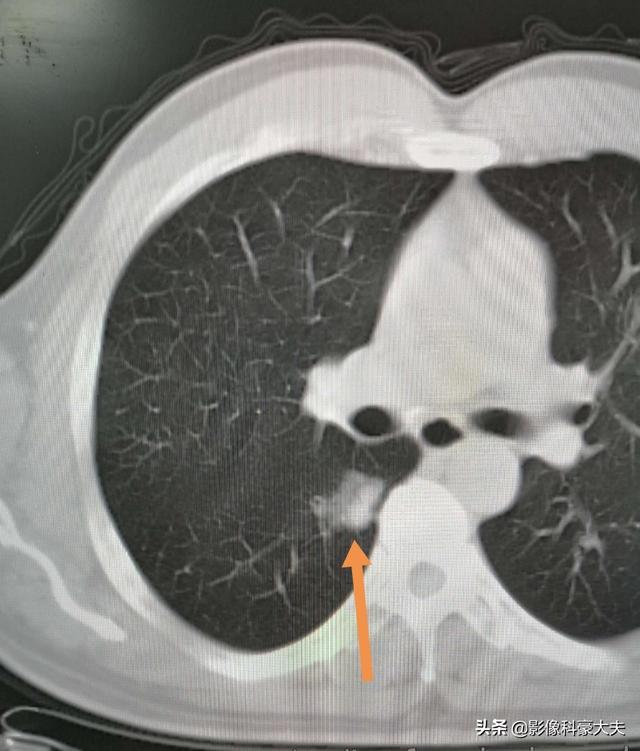

Eine sublobeare Resektion (d. h. eine segmentale Resektion oder Keilresektion) hat weniger Auswirkungen auf die Lungenfunktion, da weniger Lungengewebe entfernt wird und mehr normales Lungengewebe verbleibt. Wird eine Lobektomie durchgeführt, weil mehr Lungengewebe entfernt wird, verbleibt relativ wenig normales Lungengewebe, was sich stärker auf die Lungenfunktion auswirkt und eher zu Beschwerden in der Brust führen kann. Die folgenden Bilder zeigen die Lungen von zwei verschiedenen Resektionen: Das obere Bild zeigt die Lobektomie des rechten unteren Lungenknotens, und Sie können sehen, dass die rechte Lunge nach der Operation deutlich kleiner ist. Das untere Bild zeigt eine sublobar Resektion des linken unteren Lungenknotens, und Sie können sehen, dass die linke Lunge nach der Operation ein größeres Volumen aufweist.